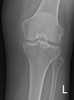

Calcific bursitis

Calcific bursitis refers to calcium deposits within the bursae. This most occurs in the shoulder area. [Source: Wikipedia ]